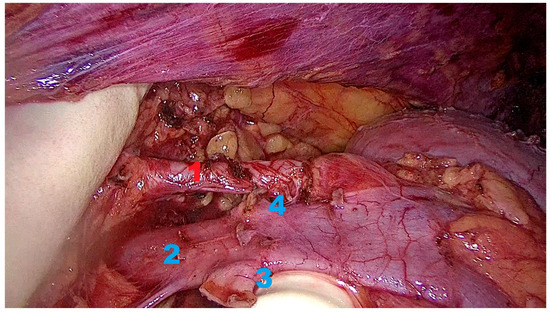

Background: Minimally invasive techniques for living donor nephrectomy are crucial for donor safety and promoting organ donation. Hand-Assisted Retroperitoneoscopic Donor Nephrectomy (HARP-DN) combines the benefits of minimally invasive surgery with...